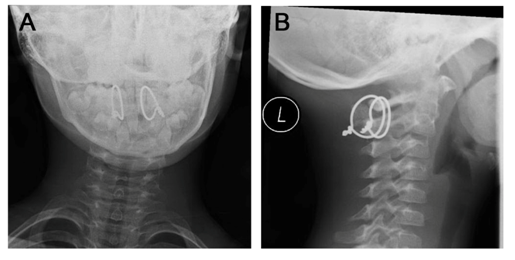

Throughout his stay on the ward, the patient remained neurologically intact, suffered no complications and was dismissed pain free after 8days (Figure 4). After six weeks of immobilization with three weeks each in a Miami-J-collar and a soft collar, the boy had regained good range of motion and was free of pain with no neurologic disabilities. Roentgen graphic controls showed no dislocation (Figure 5) and good functional results. Three month after trauma, the range of motion was flexion/extension 40/0/35°, lateral bending left/right 40/0/40° and rotation left/right 80/0/80°. The tension wires were removed six month after fusion without complications (Figure 6). Another four weeks later the range of motion was flexion/extension 70/0/80° with no chin-to-sternum-distance left, lateral bending left/right 70/0/70° and rotation left/right 80/0/90° (Table 1).

Figure 4 Postoperative x-ray control. A) AP-view with paramedian tension wires. B) Lateral view.

Figure 5 Functional radiographs. A) AP-view in neutral position. B) Lateral view of head flexion. C) Lateral view of head extension.

Figure 6 Lateral view x-ray before and after removal of tension wires. A) Before removal, 3month after trauma. B) After removal, with an 8-mm drain in situ.